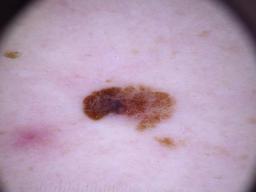

Training set from the ISIC 2018 Challenge.

[1] Noel Codella, Veronica Rotemberg, Philipp Tschandl, M. Emre Celebi, Stephen Dusza, David Gutman, Brian Helba, Aadi Kalloo, Konstantinos Liopyris, Michael Marchetti, Harald Kittler, Allan Halpern: "Skin Lesion Analysis Toward Melanoma Detection 2018: A Challenge Hosted by the International Skin Imaging Collaboration (ISIC)", 2018; arxiv.org/abs/1902.03368

[2] Tschandl, P., Rosendahl, C. & Kittler, H. The HAM10000 dataset, a large collection of multi-source dermatoscopic images of common pigmented skin lesions. Sci. Data 5, 180161 doi:10.1038/sdata.2018.161 (2018).